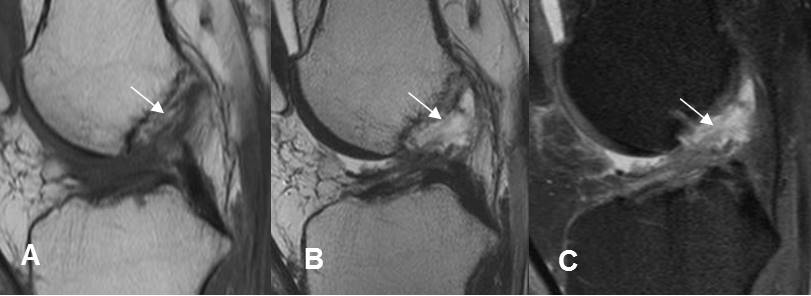

Fig 165. Esguince GII.

A: RM sagital en T2 y B: RM sagital en STIR. Adelgazamiento, con solución de continuidad en la mayoría de las fibras del LCA, por ruptura parcial.

Fig 166. Esguince G III.

A: RM sagital en T1, B: RM sagital en T2 y C: RM sagital en STIR. Ruptura completa del LCA en su origen femoral, con cambios inflamatorios agudos.